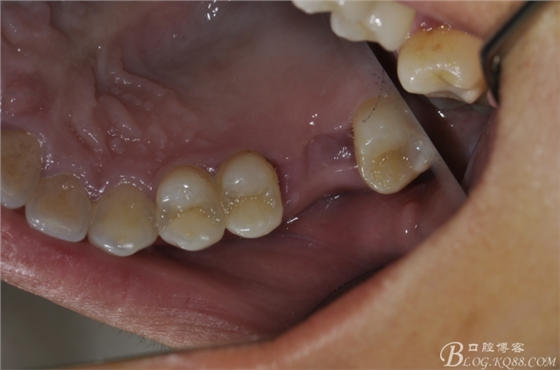

修復(fù)后口內(nèi)照片